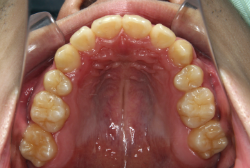

叢生(そうせい)

凸凹な歯並びのことを叢生といいます。矯正歯科に来院する患者様の主訴の中で、最も多いのが「配列の凸凹を真っ直ぐにしたい」というものです。歯の大きさと顎の大きさの調和がとれていないことが原因です。

凸凹を主体としたケースの場合、当院の平均治療期間は18ヶ月ですので、このケースは少し長めに経過しました。理由の一つは凸凹の程度がかなり重症だったと言うことですが、もう一つは、右下第2大臼歯が45度くらい前傾していたため、それを整直化させるために時間を要したと考えています。いずれにしても最終結果は大変よい状態と思います。

治療前は並びが乱れて見た目が悪いというのはもちろん問題ですが、歯科医学的に一番困るのは噛み合わせが悪いという点です。上下の犬歯(3番目の歯)は、上下的に離れた位置にあるため接触することができません。つまり歯としては存在していても、歯としては機能していないということです。